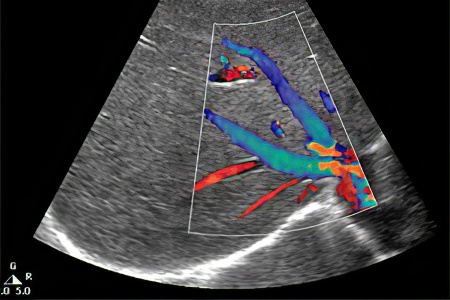

Не следует недооценивать и ультразвуковое исследование. Доплеровская ультрасонография может быть использована для выявления тромбоза почечных вен, однако стоит помнить о высокой вероятности получения ложноотрицательных результатов.